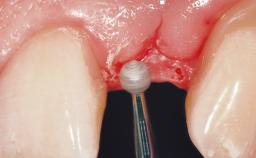

Early Placement of an Implant in a Maxillary Right Central Incisor Site

This 41-year-old female patient was referred to the clinic for the replacement of the right central incisor, since the tooth had developed a root fracture in the long axis that made extraction necessary. The healthy, non-smoking patient was first seen with the tooth still in place. A detailed Esthetic Risk Assessment was performed.The patient was worried about her dental esthetics and had high expectations for a successful treatment outcome from an esthetic point of view. The patient had a medium lip line that displayed parts of the gingiva in the anterior maxilla upon smile.

Bone Augmentation Horizontal|Simultaneous

Augmentation Materials Autogenous chips|Xenogenous|Membrane